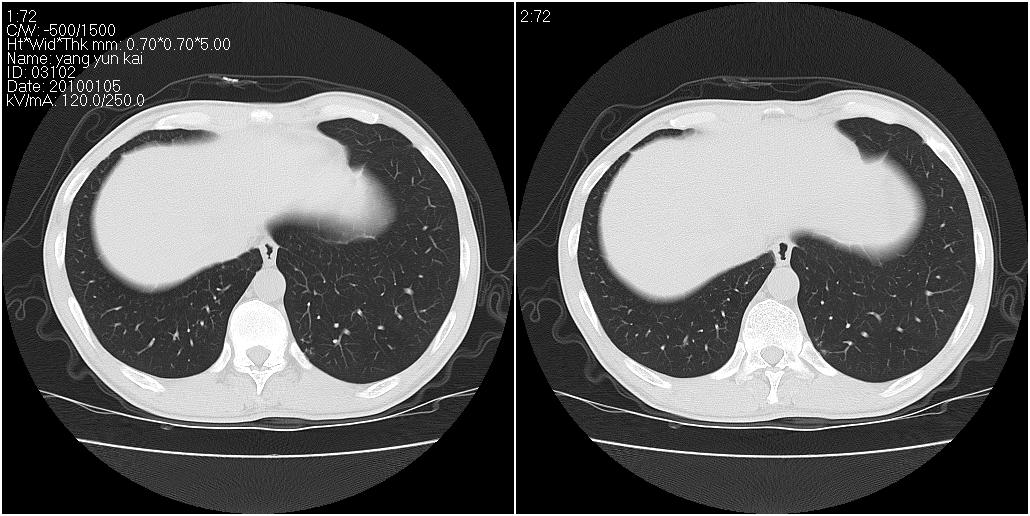

标题: CT23980:男性,47岁。近来咳痰、咳血,血沉增快(40左右),

男性,47岁。近来咳痰、咳血,血沉增快(40左右),痰中未检出结核杆菌。

两肺继发性肺结核并多发性结核球形成,部分病灶内空洞形成。